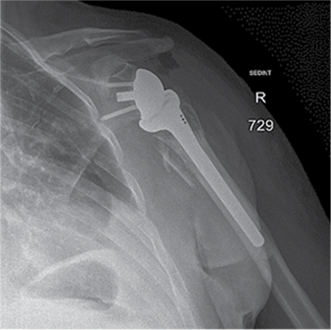

Figure 3. X-ray after shoulder arthroplasty

In a subsequent consultation, it was decided to perform shoulder arthroplasty 11 days later using reverse prosthesis (Delta Xtend, DePuy Synthes) with tuberosity fixation.

Postoperative course was uneventful in the chest or shoulder. The patient was discharged after 23 days from admition.